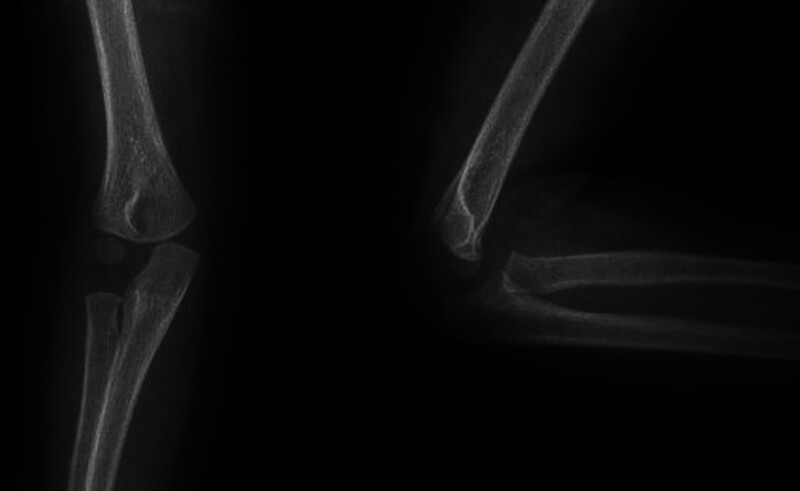

小儿肱骨外侧髁骨折(PHLCF)是儿童中最常见的骨折之一。PHLCF约占所有小儿肘部骨折的20%。治疗方法包括:夹板固定的非手术治疗、经皮K线固定闭合复位术(CRPP)和K线固定开放复位术(ORIF)。我们的目的是评估采用 CRPP 或 ORIF 治疗 Jakob 2 型 PHLCF 的放射学、功能和临床疗效。我们假设 CRPP 与 ORIF 对 Jakob 2 型 PHLCF 的治疗同样安全有效。在这项回顾性研究中,我们纳入了在一个中心接受手术治疗的 Jakob 2 型 PHLCF 患者。研究排除了多发性骨折或开放性骨折患者。研究共纳入 69 名 2 至 12 岁的患者,并将他们分为两组。第一组包括接受 CRPP 治疗的患者,第二组包括接受 ORIF 治疗的患者。研究人员对患者的人口统计学、放射学、临床和功能参数进行了评估。平均手术时间(P

Pediatric humerus lateral condyle fractures (PHLCF) are one of the most common fractures among children. PHLCF is approximately 20% of all pediatric elbow fractures. Among the treatment modalities are: nonoperative treatment with splinting, closed reduction with percutaneous K-wire fixation (CRPP), and open reduction with K-wire fixation (ORIF). We aimed to evaluate radiological, functional, and clinical outcomes of Jakob type 2 PHLCF treated either with CRPP or ORIF. We hypothesized that CRPP may be as safe and effective as ORIF for Jakob type 2 PHLCF. In this retrospective study, we included patients with Jakob type 2 PHLCF operatively treated in a single center. Patients with multiple fractures or open fractures were excluded from the study. 69 patients between ages 2 and 12 were included and they were divided into two groups. Group 1 included the patients treated with CRPP, whereas Group 2 included the patients treated with ORIF. Demographical, radiological, clinical, and functional parameters were evaluated. Average duration of surgery ( P  < 0.001), initial displacement ( P  = 0.014), and duration of admission ( P  < 0.001) were significantly less in group 1. Group 2 had significantly higher percentage of left-sided injury than group 1 ( P  = 0.038). Average varus deformity score was significantly higher in group 1 ( P  = 0.014). CRPP was associated with shorter duration of surgery and hospital stay. Functional, clinical, and radiological outcomes were identified similar between CRPP and ORIF for Jakob type 2 PHLCF. CRPP may be as safe and effective as ORIF for Jakob type 2 PHLCF.